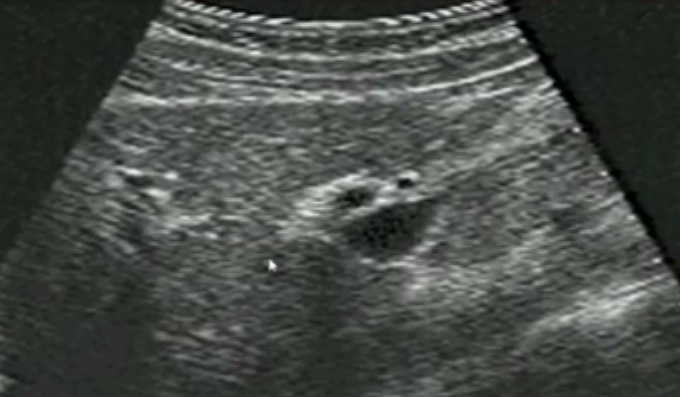

一、正常膽囊超聲圖像有的時(shí)候經(jīng)常發(fā)現(xiàn)檢查不到膽囊,其實(shí)有幾種可能性,檢查人員的技術(shù)不過(guò)關(guān)沒(méi)發(fā)現(xiàn)膽囊,就要找上級(jí)醫(yī)生會(huì)診,如果還是沒(méi)找到的話就不是技術(shù)問(wèn)題。結(jié)石或腫瘤充滿膽囊,使其液腔消失,慢性膽囊炎使得膽囊萎縮或膽囊壁肥厚而囊腔消失患者已進(jìn)食,膽囊處于膽汁排空的狀態(tài),膽囊先天性過(guò)小或缺失;膽囊位置極端異常(可能很低或位于左側(cè))膽囊切除術(shù)后(注意詢問(wèn)病史)。